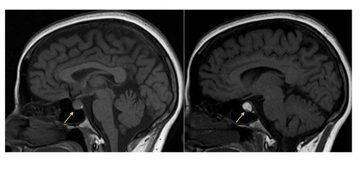

Apopleksi, beyin damarlarından birinde ani yırtılma sonucu veya tıkanma sonucu gelişen bilinç kaybı ve felç oluşumuyla belirgin tabloya denir. Apoplexy